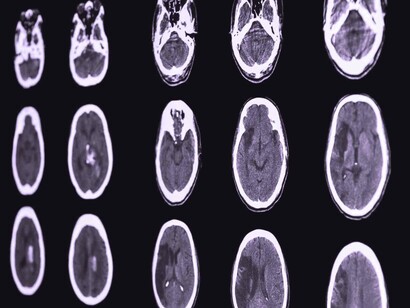

Se está observando la presencia de ictus o accidentes cerebrovasculares (ACV) en adultos jóvenes (menores de 50 años) sin factores de riesgo cardiovascular que sufren COVID-19. Es decir, personas sin la edad ni los factores de riesgo suficientes como para esperar un ictus. Se especula si realmente hay un aumento significativo, pues aún se han descrito pocos casos, o si realmente la infección favorece el desarrollo de estos.

En un artículo publicado en The Lancet del pasado mes de abril, se trata el tema de por qué los accidentes cerebrovasculares están ocurriendo en jóvenes aparentemente sanos. En dicho artículo, investigadores del Hospital Universitario de Zúrich notaron que el virus SARS-CoV-2 (COVID-19) infecta a los huéspedes a través de la enzima convertidora de angiotensina (ACE2), expresado no solo en los pulmones sino también en el corazón, riñón, intestino y células endoteliales. Y describieron tres casos en los que observaron infección viral directa de las células e inflamación endotelial difusa (endotelitis). La endotelitis por COVID-19 podría explicar la función microcirculatoria deteriorada en diferentes lechos vasculares y sus secuelas clínicas en pacientes con COVID-19.

Investigadores holandeses describieron otro posible mecanismo detrás del aparente aumento del riesgo de accidente cerebrovascular en un artículo publicado en línea, en abril, en la revista Thrombosis Research. En 184 pacientes de la UCI con neumonía comprobada por COVID-19, se observó un resultado de embolia pulmonar aguda sintomática, trombosis venosa profunda, accidente cerebrovascular isquémico, infarto de miocardio o embolia arterial sistémica en un 31%, una cifra que llamaron «notablemente» alta. Se especula un problema con el sistema de coagulación o con el revestimiento endotelial de los vasos sanguíneos.

Cualquiera que sea la causa del mayor riesgo de accidente cerebrovascular asociado con COVID-19, se ha visto que, tanto la presentación como el resultado, son a menudo peores que en otros accidentes cerebrovasculares. Por lo general, estos pacientes con COVID-19 presentan más de un vaso bloqueado con un trombo. En el estudio de una serie de casos, la mortalidad fue de alrededor del 55 por ciento. A pesar de reabrir los vasos obstruidos, terminan teniendo otro ictus importante. Su sangre sigue coagulándose con rapidez.